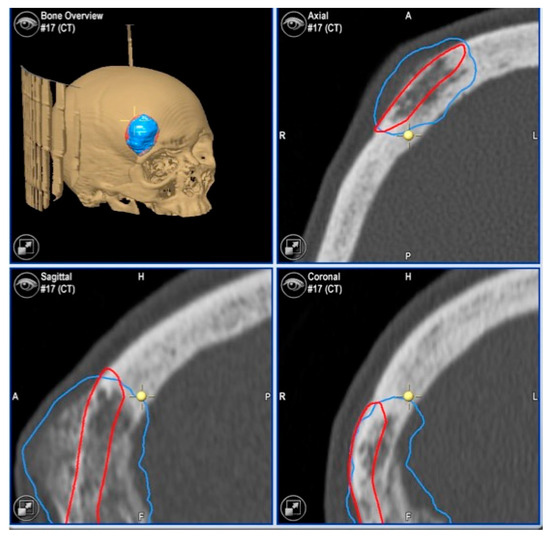

2.3.1. Virtual Surgical Plan

| 1 | 53/F | L/25 mm | Y | 4 mo | Dystopia | N | CT, MRI | Supraorbital rim, orbital roof | Intraosseous venous malformation | - | Resection + reconstruction | Y | Y | 1st, 2nd, 3rd | Coronal | Y | Piezoelectric device | N | PEEK prosthesis | 7 y/N |

| 2 | 54/F | R/33 mm | Y | 9 y | N | Y | CT, MRI | Frontal bone, orbital roof | Intraosseous venous malformation | - | Resection + reconstruction | Y | Y | 1st, 2nd, 3rd | Coronal | Y | Piezoelectric device | N | PEEK prosthesis | 6 y/N |